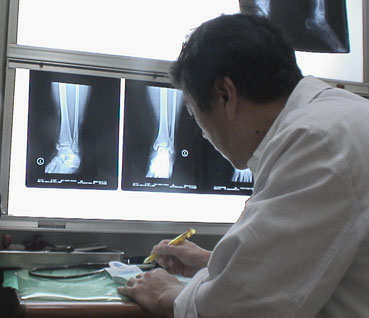

すぐ、延吉にある延辺大学病院で、診察をしてもらった。レントゲンを撮ってみると足の骨が折れていた。

診察をし、レントゲンを撮ったりして、即、入院をすることになった。

| 初診は伊藤先生が見てくださった。「約、2ヶ月ですな。1年経てば、まだ山に登れるよ」 | |||||